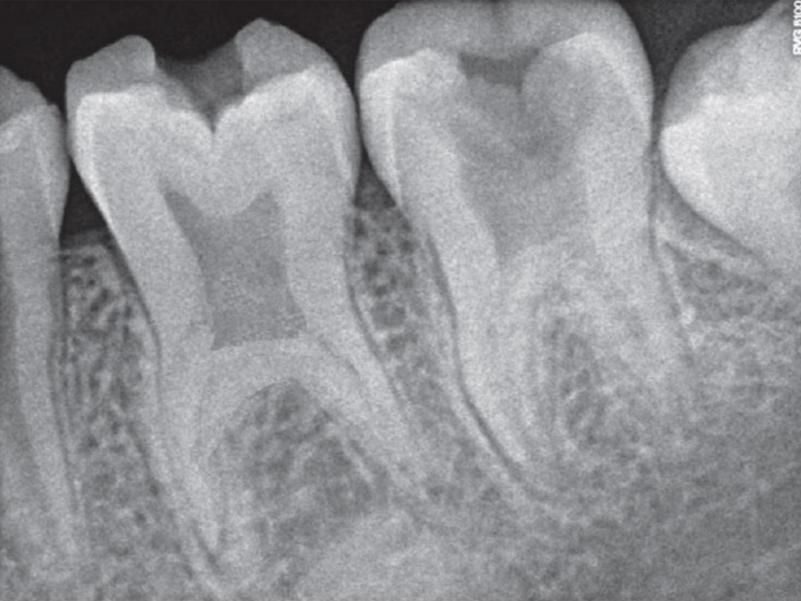

Radiographic features

- An enlarged pulp chamber is seen.

- The roots of the tooth get smaller.

- Furcation is present just above the root apex.

Visual radiographic assessment is the most followed method of diagnosing taurodontism. By using this method, severe forms of taurodontism can be easily recognized without much difficulty.